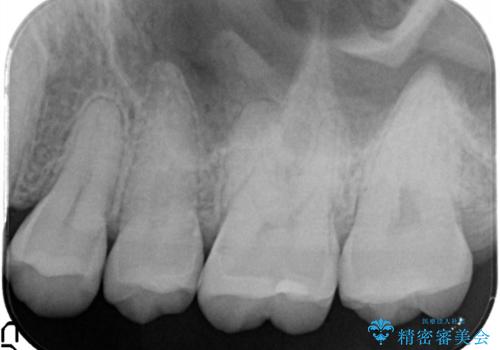

虫歯の再発リスクを減らすセラミックインレー

- 他院でインビザラインの治療中に虫歯を発見されたため、治療を希望され来院された患者様です。

セラミックインレーにて治療を行いました。

セラミックインレーは適合が良く、虫歯の再発リスクを減らすことができます。